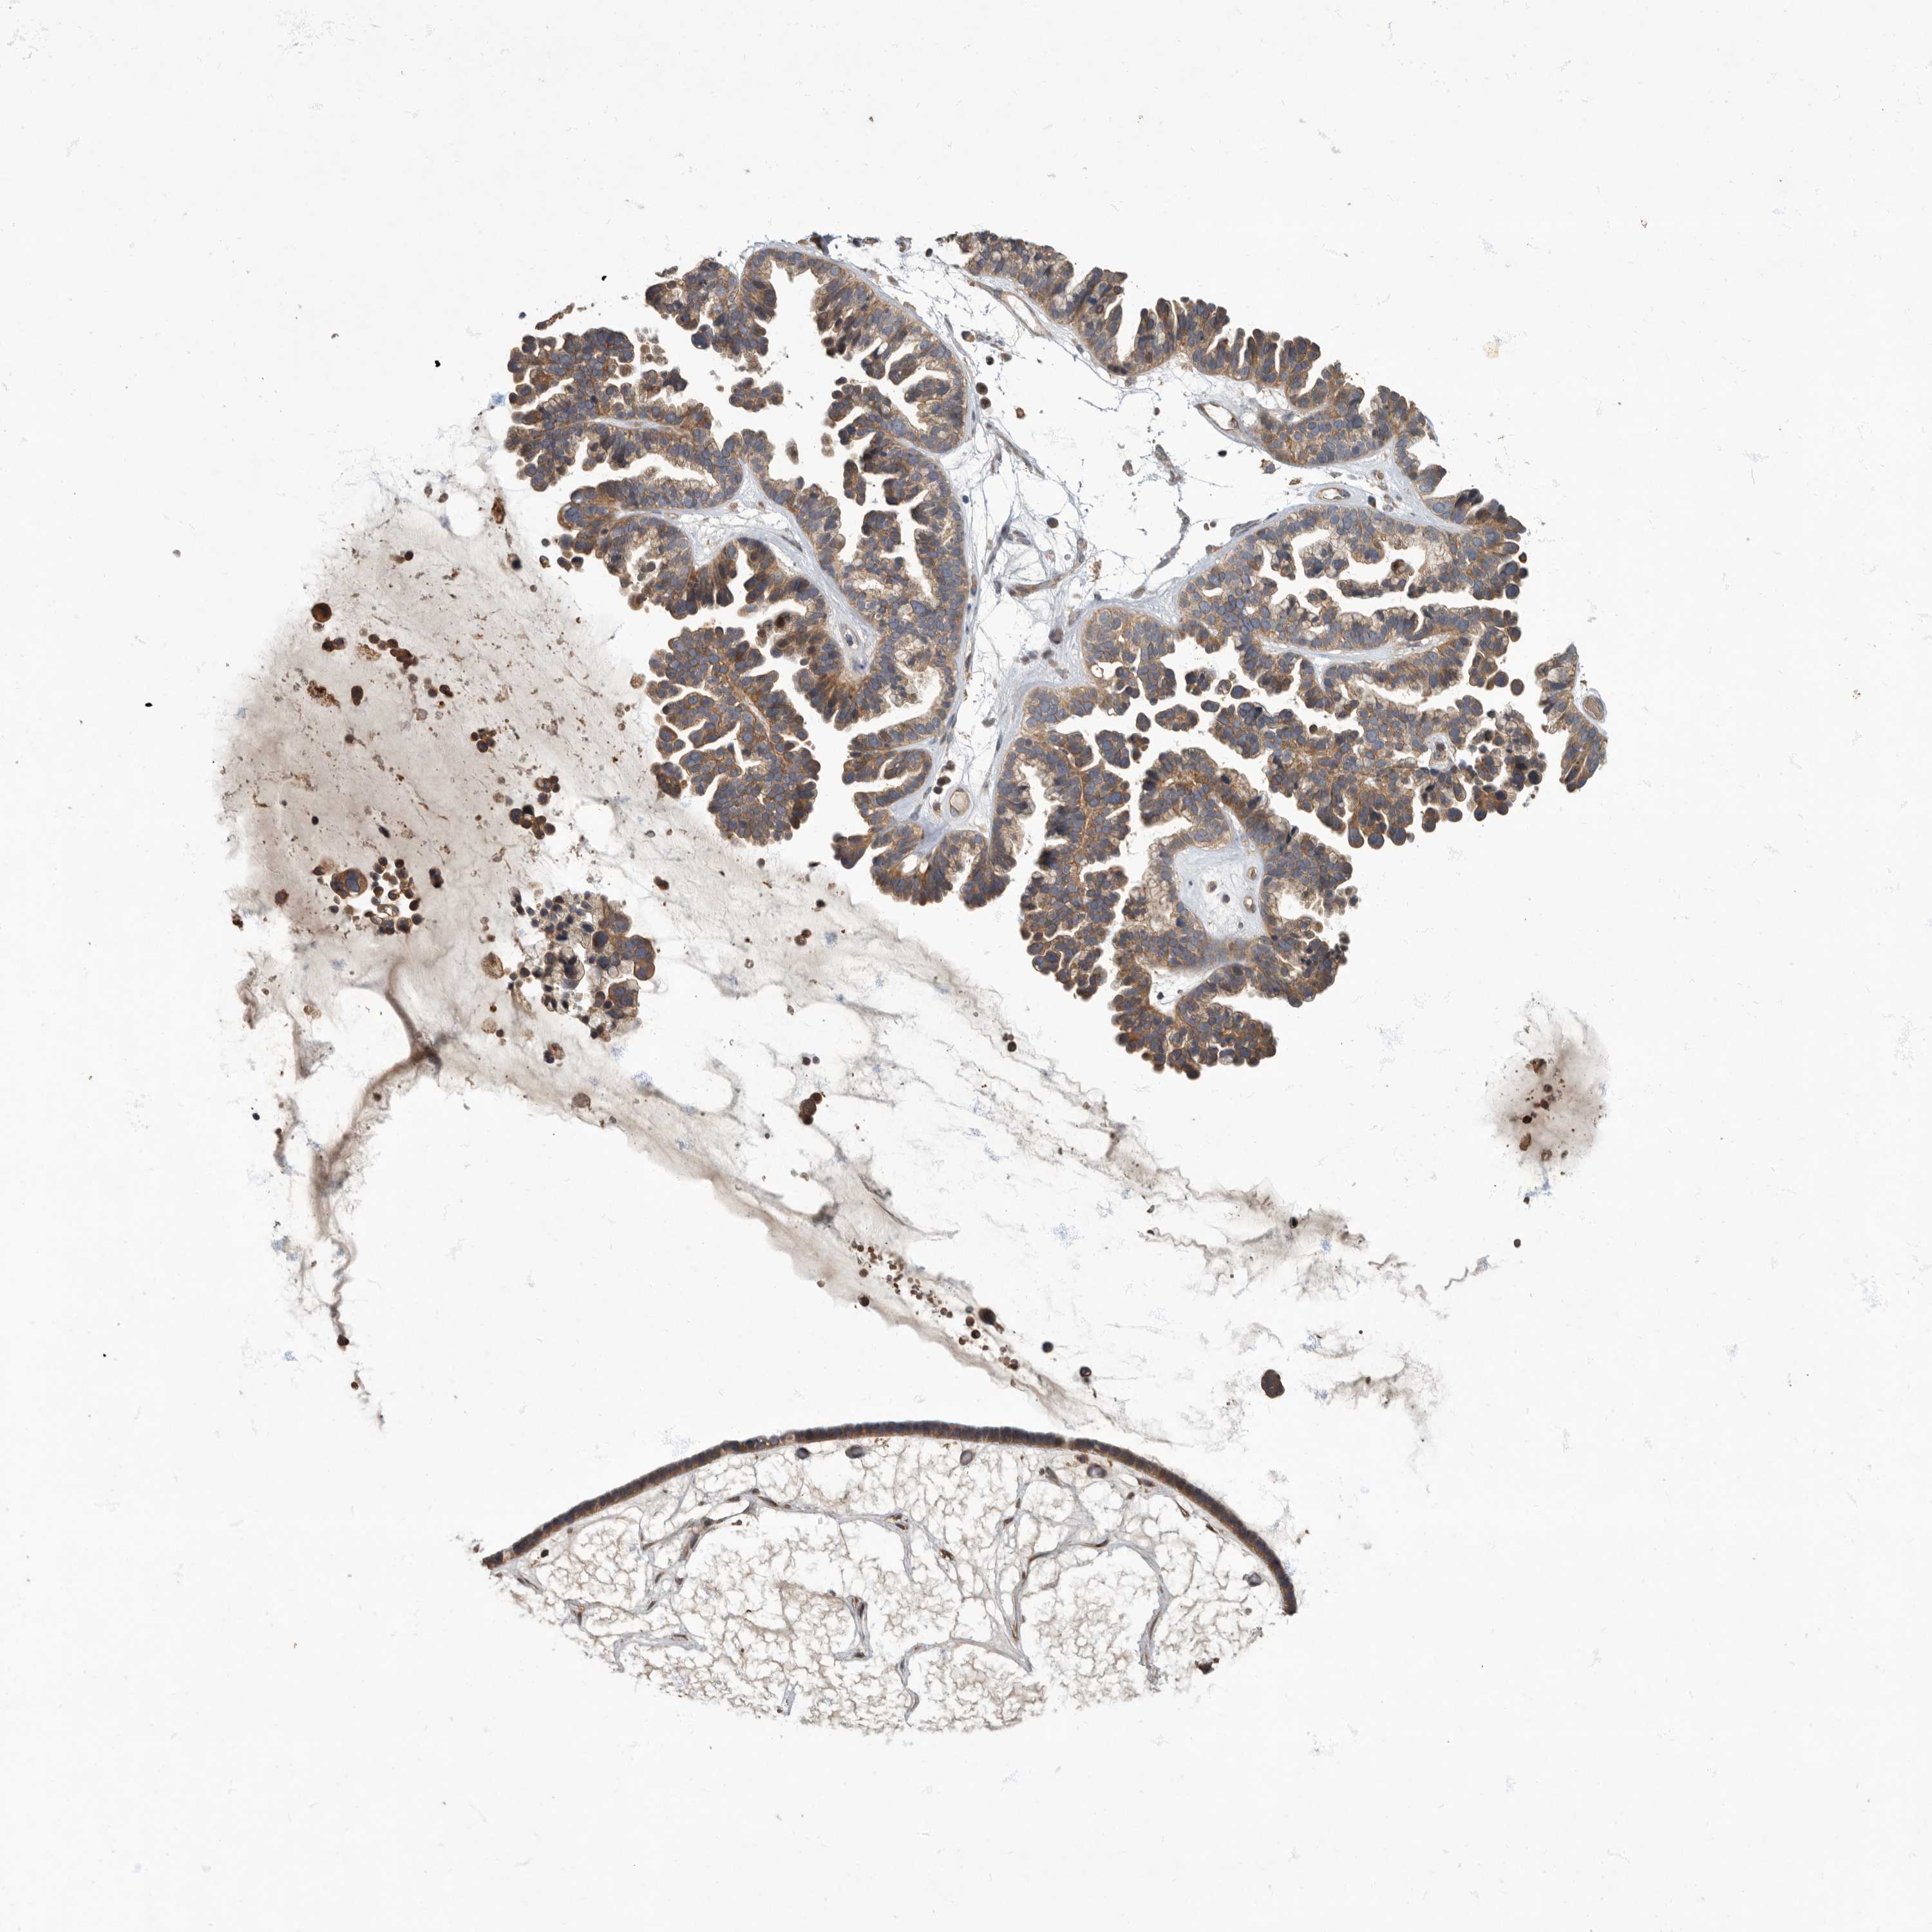

OVARIAN CANCER - Protein expressioni

A mouse-over function shows sample information and annotation data. Click on an image to view it in a full screen mode. Samples can be filtered based on level of antibody staining by selecting one or several of the following categories: high, medium, low and not detected. The assay and annotation is described here.

Note that samples used for immunohistochemistry by the Human Protein Atlas do not correspond to samples in the TCGA dataset.

Antibody stainingi

Antibody staining in the annotated cell types in the current human tissue is reported as not detected, low, medium, or high, based on conventional immunohistochemistry profiling in selected tissues. This score is based on the combination of the staining intensity and fraction of stained cells.

Each image is clickable and will lead to virtual microscopy that enables deeper exploration of all samples and also displays staining intensity scores, fraction scores and subcellular localization as well as patient and tissue information for each sample.

Antibody HPA026792

Staining

High

Medium

Low

Not detected

Intensity

Strong

Moderate

Weak

Negative

Quantity

>75%

75%-25%

<25%

None

Location

Nuclear

Cytoplasmic/membranous

Cytoplasmic/membranous,nuclear

Cystadenocarcinoma, serous, NOS

Carcinoma, endometroid

Cystadenocarcinoma, mucinous, NOS

Carcinoma, NOS